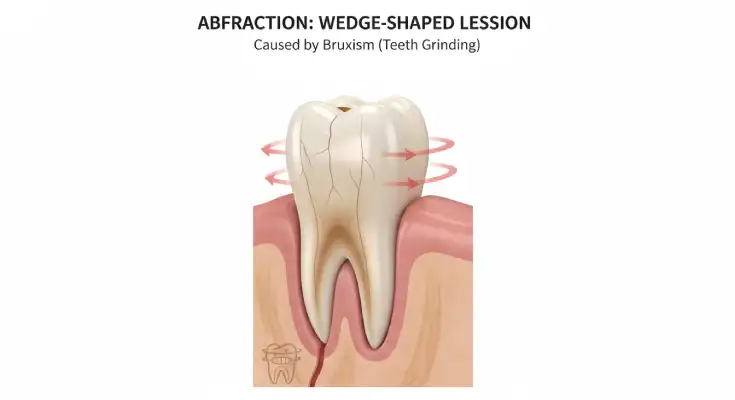

3. Biomechanical Stress (Abfraction)

Another hidden cause of gum-line erosion is something dentists call abfraction, a fancy term for damage caused by tooth flexing.

If you grind or clench your teeth (a condition known as bruxism), especially during sleep, the constant pressure causes your teeth to bend slightly at their narrowest point, right near the gum line. This repeated flexing creates tiny cracks or wedge-shaped notches in the enamel.

Over time, these microscopic stresses can cause the enamel and dentin to chip away, even if your brushing and diet are perfect. You might notice sharp sensitivity or visible grooves near your gums, often on the side teeth.

Step 4: Treat Grinding or Gum Issues

Sometimes, erosion is linked to mechanical stress or gum health problems, and those need special care too.

For teeth grinding (bruxism):

If you clench or grind your teeth, especially at night, your dentist may suggest a custom-made night guard. This protects your teeth from pressure and helps prevent new damage.For gum recession: